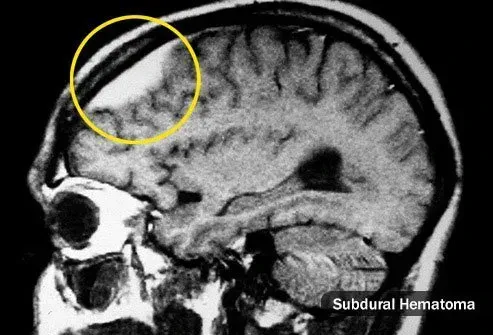

Tu te frappe la tête

Les maux de tête peuvent commencer immédiatement ou des mois après une blessure. Ils pourraient être sur le site du coup ou partout dans votre crâne et peuvent empirer lorsque vous êtes stressé. La cause n'est pas toujours claire mais parfois trop de sang s'accumule à un seul endroit. C'est ce qu'on appelle un hématome. Dans les cas graves, vous pouvez vous sentir faible confus nauséeux et oublieux. Consultez votre médecin si vous avez l'un de ces symptômes ou si vous avez mal à la tête après avoir frappé la tête.